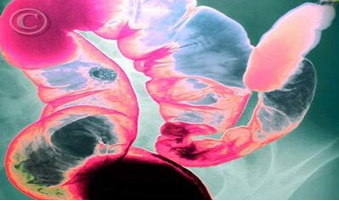

5. Phương pháp X-quang, chụp cộng hưởng từ (MRI), quét tia X trên máy tính (CAT) để tìm ký sinh trùng

Những kỹ thuật này được sử dụng để tìm một số bệnh ký sinh trùng có thể gây ra tổn thương trong các cơ quan như: tim, gan, phổi, não, ruột, cơ….

Hình 5 : Trùng lông Balantidium coli (x) ký sinh trong ruột qua phim Xray.

(nguồn:http://suckhoedoisong.vn/trung-long-balantidium-co-the-gay-thung-ruot-n48849.html)